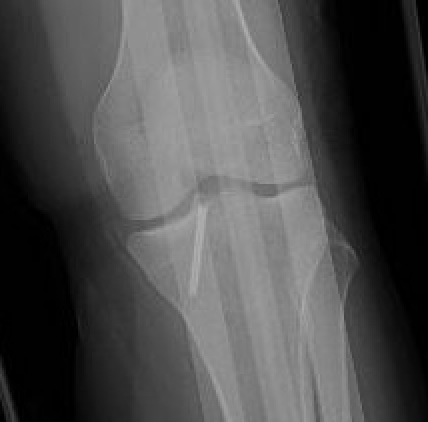

Xray

Xray showing likely Type II with anterior hinging

Type II / III